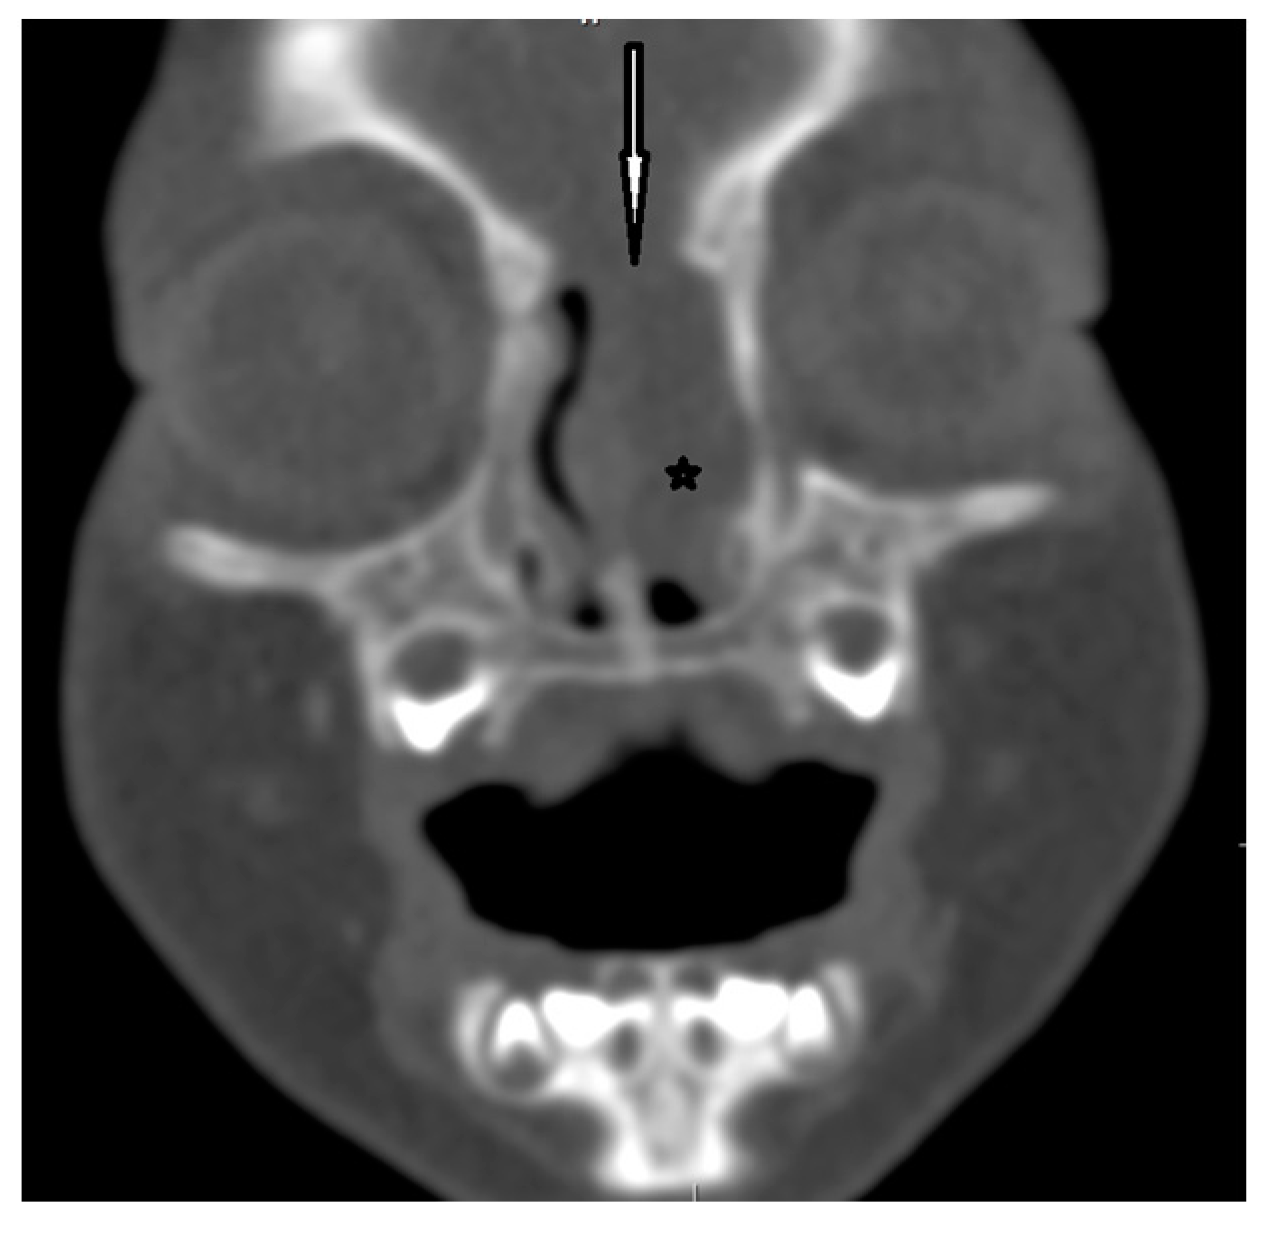

| Radiological characteristics | CT | No correlation between the particular location of the sinus ostium or cyst and the presence of intracranial extension; bifid crista galli and widening of foramen caecum (suggestive of intracranial extension); dermoid cyst—density of fat; epidermoid cyst—density of water | Bony defect may be revelaed | Developmental bony defect of the skull base |

| MRI | Variable signal intensity depending on the protein content; fat-suppressed T1-weighted images—differentiation between skull base defects and enhancing non-ossified cartilage of anterior cranial fossa; DWI—typically high-signal-intensity lesion with corresponding low signal intensity on ADC maps | Discontinuity with the brain parenchyma; variable visualization of a fibrous stalk connection to CNS; well-circumscribed, rounded, or polypoid mass—isointense or rarely hypointense to gray matter on T1-weighted imaging; neural tissue—more hyperintense on T2-weighted images to normal brain parenchyma in most cases; dysplastic tissue usually corresponds with no enhancement or moderate enhancement; noticeable enhancement at the lesion periphery | Herniation of intracranial tissue and its continuity with the brain | |